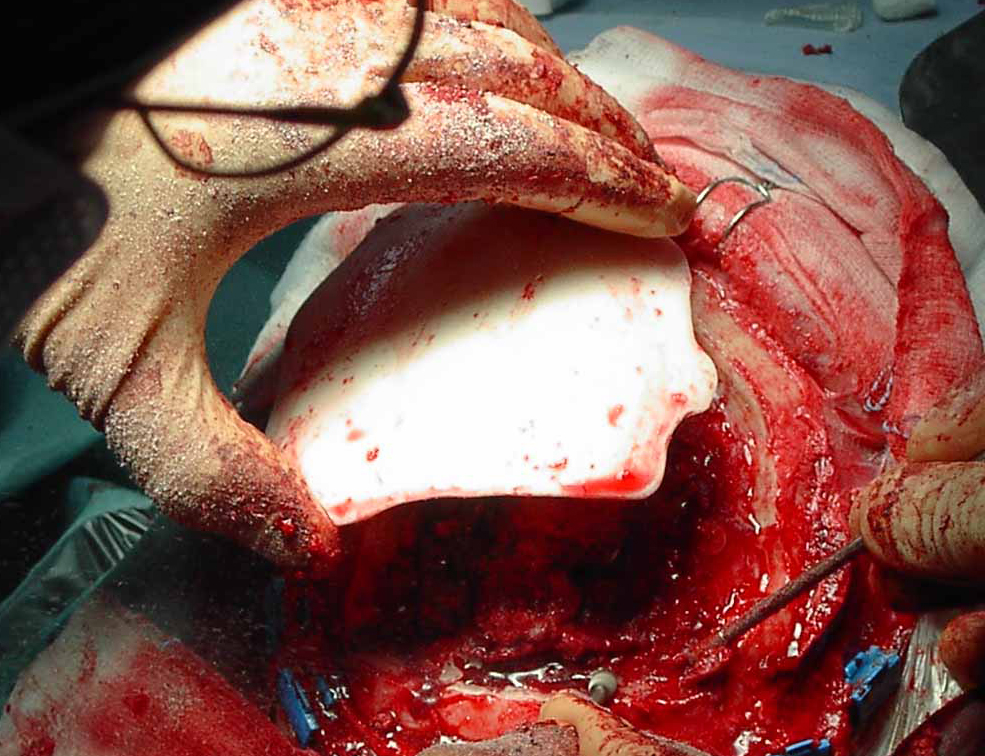

Demolizione/ricostruzione

cranica in un unico tempo |

| Meningioma

con demolizione-ricostruzione della teca cranica in un unico tempo

con tecnica microchirurgica e neuronavigazione. |